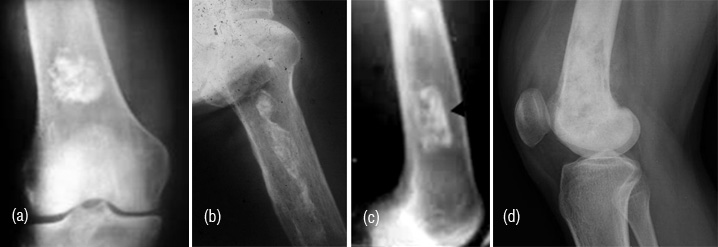

These are often encountered as circumscribed homogenous dense lesions on plain films. The size may range from few millimetres to a centimetre and may simulate osteoid osteoma which has typical radiological findings such as a nidus and surrounding reaction (Figure 1ab). It may grow and assume a large size when it is called a giant bone island (Figure 1c). Developmentally, these bone islands are cortical inclusions in trabecular bone. They may be multiple and involve many bones, and should not be mistaken for osteopoikilosis (Figure 1d).

Figures 1a,b,c,d: a) Bone island in capitate, b) Osteoid osteoma, c) Giant bone island in iliac bone, d) Osteopoikilosis.